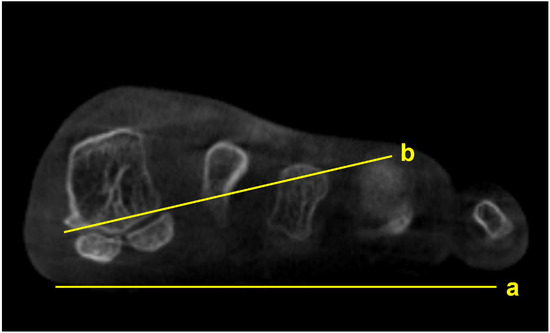

Several studies focused on the impact of M1 pronation after hallux surgery. Conti et al. conducted a study to determine if a postoperative decrease in M1 pronation observed in WBCT would be associated with changes in patient-reported outcomes [15]. Patients who underwent a modified Lapidus procedure for hallux valgus were divided into two groups with regards to the amount of postoperative M1 pronation change, and the Patient Reported Outcomes Measurement Information System (PROMIS) scores were compared between groups. At 2 years postoperatively, patients who had a significant decrease in M1 pronation after the modified Lapidus procedure showed greater improvement in the PROMIS physical function domain. Choi et al. utilized simulated weight-bearing CT to evaluate the association between preoperative M1 pronation and postoperative recurrence after proximal chevron osteotomy [16]. To quantify the amount of preoperative M1 pronation, the authors measured the M1 pronation angle (M1PA) (Figure 3). They reported that patients who had significant correction loss 1 year after surgery exhibited higher preoperative M1PA, with a 28.4-degree threshold. These results show the importance of recognizing preoperative M1 pronation through WBCT because the rotational component of the hallux valgus deformity would impact postoperative outcomes and recurrence rates after surgery.

Figure 3.

M1 pronation angle (M1PA) is the angle between the floor (a) and a line drawn from the most inferomedial border of the medial sesamoid facet to the most lateral border of the lateral sesamoid facet (b).